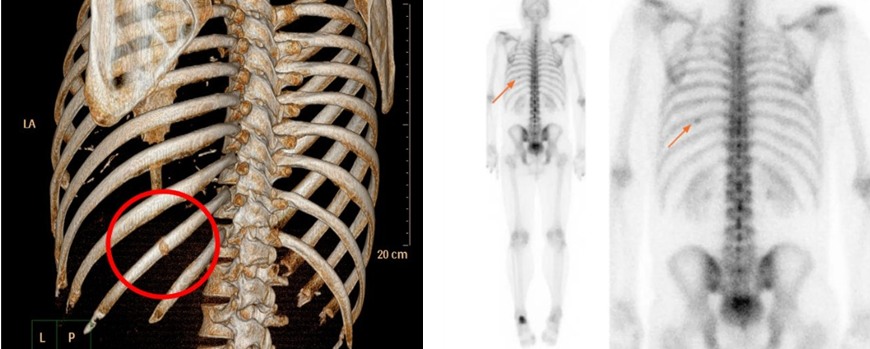

영상 검사: X-ray, CT, MRI 등으로 피로골절 확인

골스캔: 미세 골절이 X-ray에서 잘 보이지 않을 때 시행